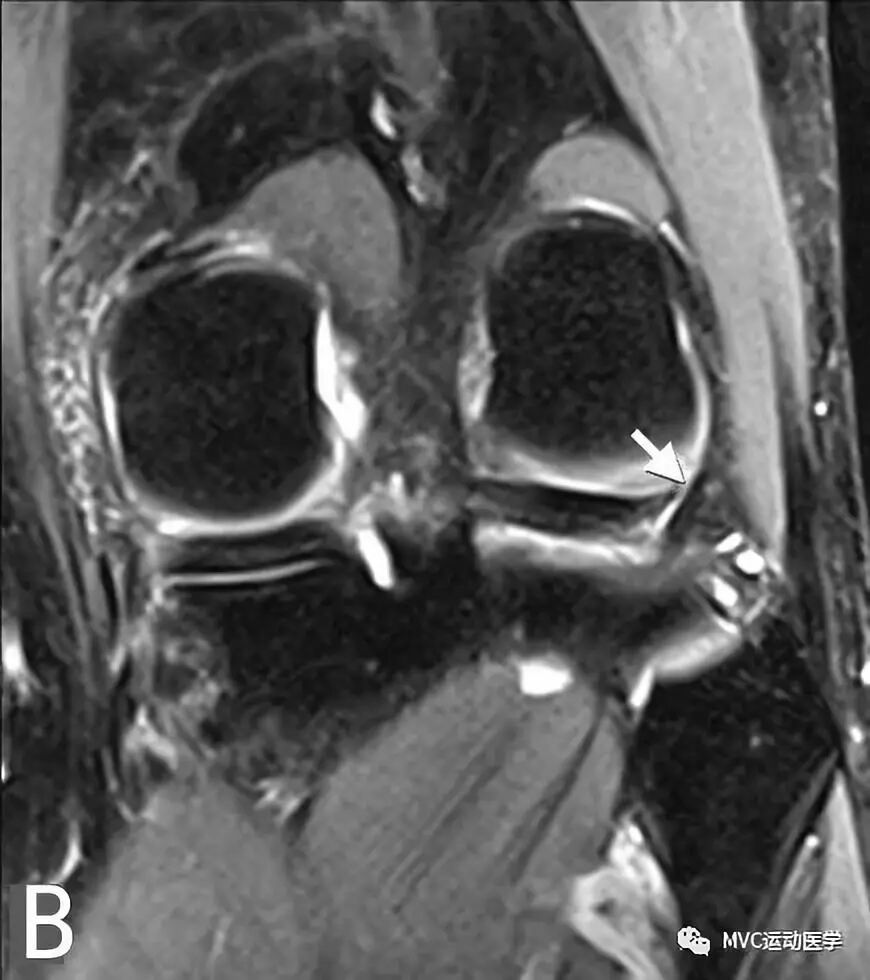

B:冠状位MRI显示腘肌腱(白色箭头)穿过腘肌腱裂孔;

A:冠状位MRI显示外侧半月板后角(白色粗箭头)与Wrisberg韧带(白色细箭头),P代表后交叉韧带

B:矢状位MRI连续扫描,黑色箭头所指为Wrisberg韧带